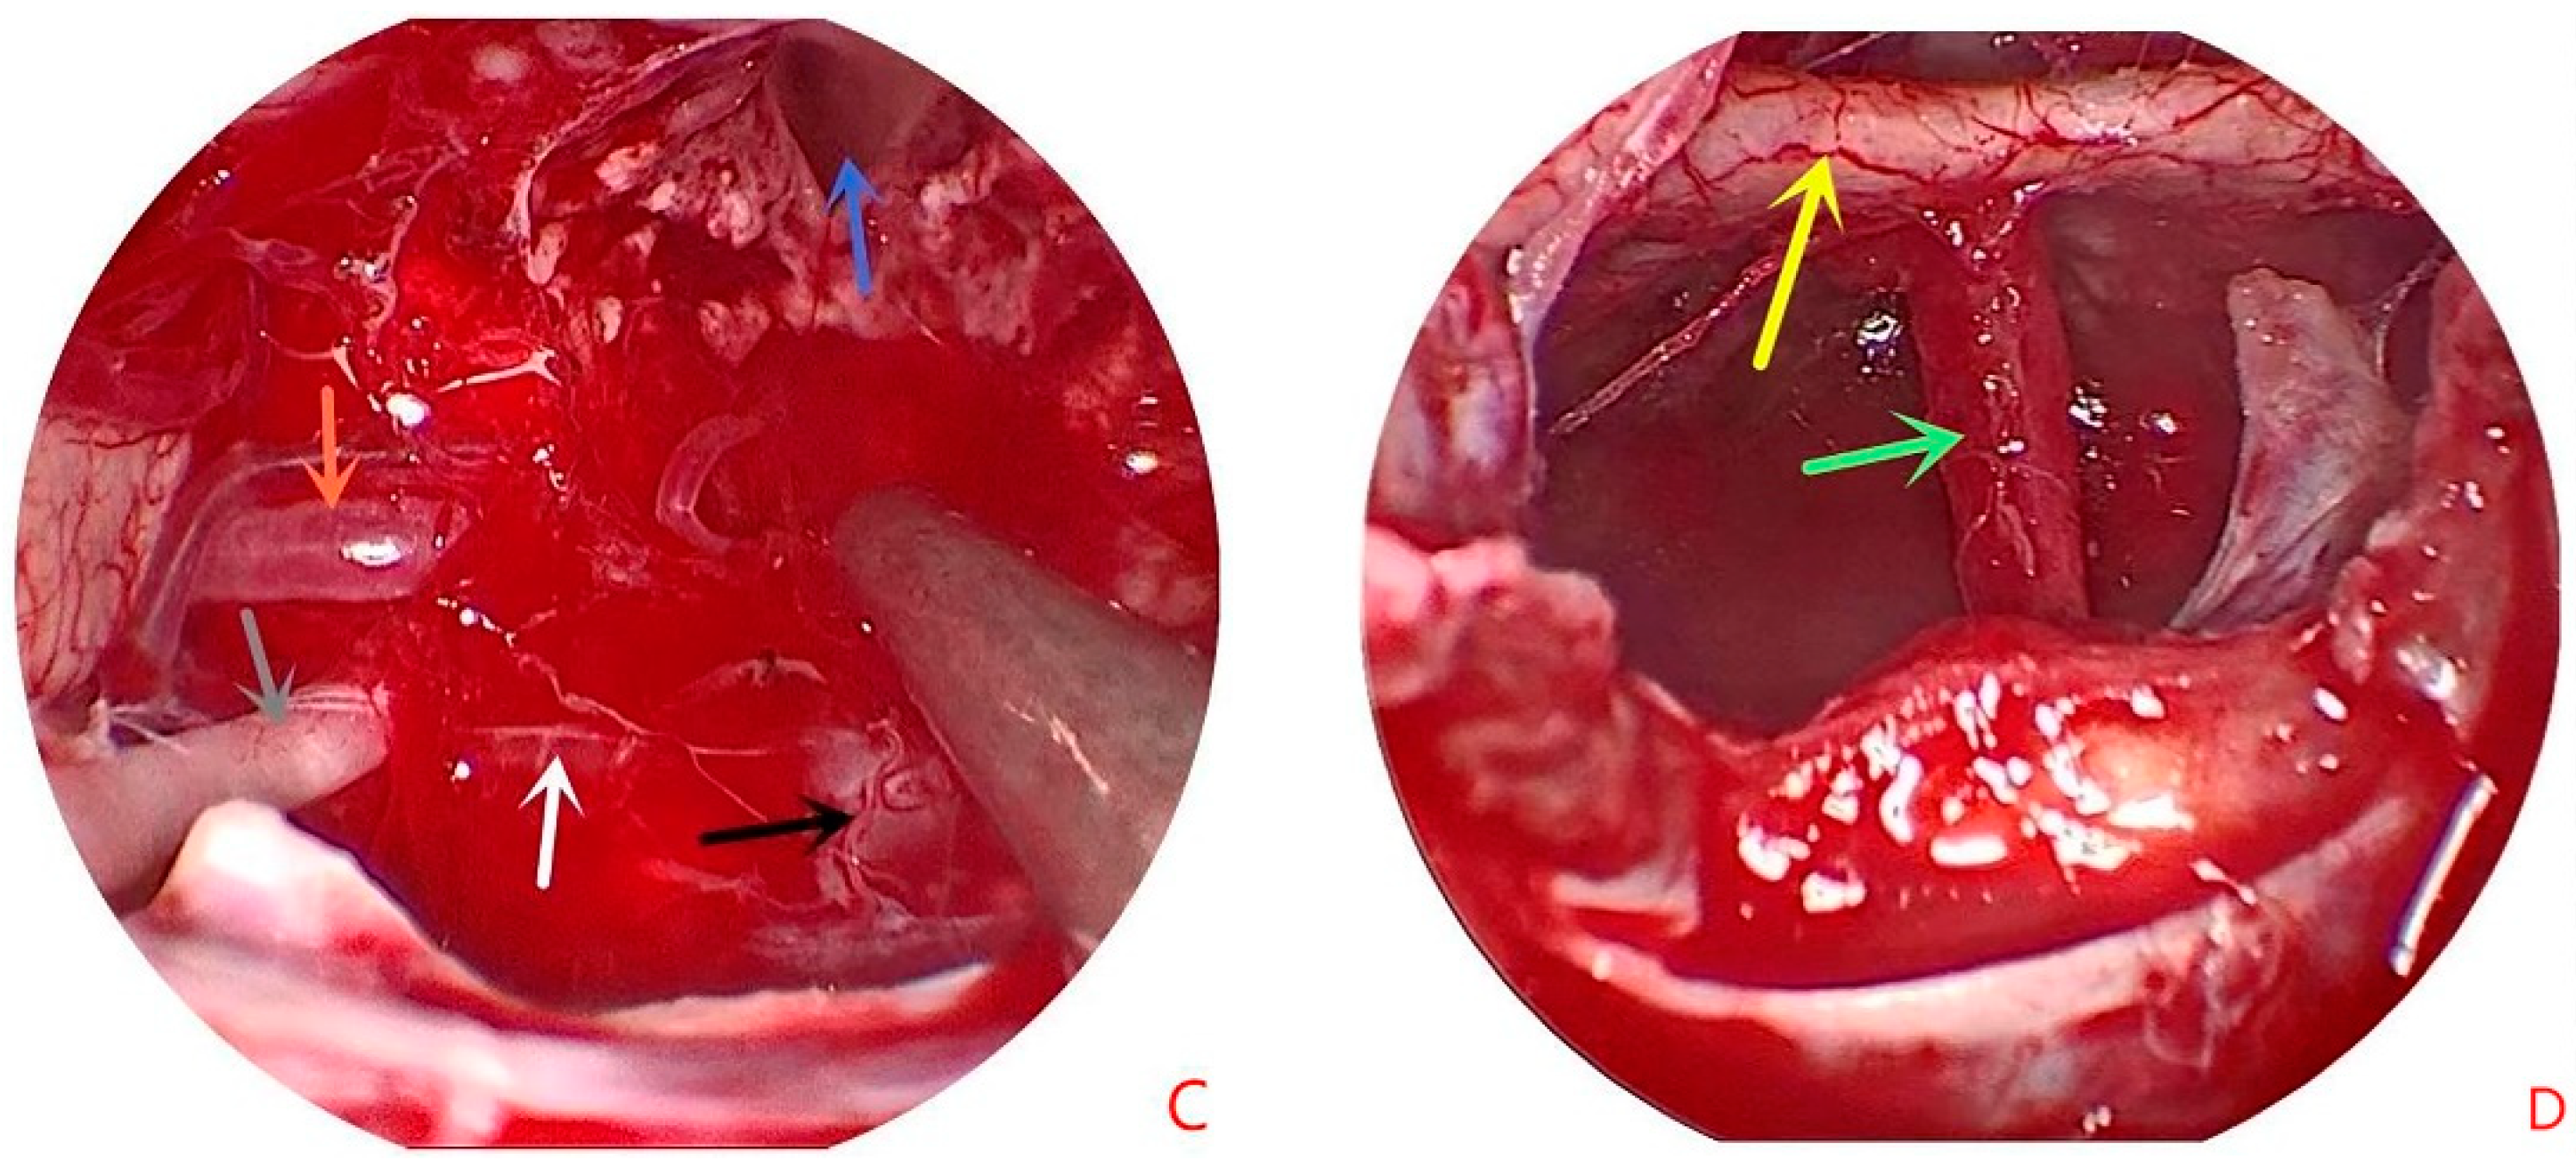

2. Patient Information

3. Operative Note